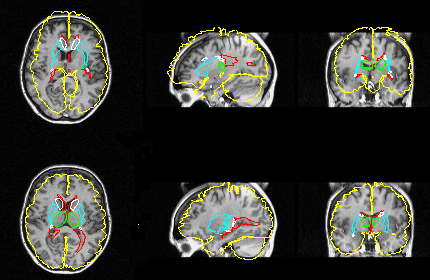

PET data before (upper row) and after (lower row) fully automatic matching of the atlas

Automatic detection of hypoperfused areas in SPECT

The fully automatic intersubject registration technique in CBA allows for reference images

representing "normality" to be created by averaging images from helthy volunteers.

Images from a patient can then, after a preceeding normalization of anatomy and intensity,

be subtracted from the reference volume. Deviations in the patient data from the normal

state can be detected in this way and can be displayed in subtration images and t-test

images.